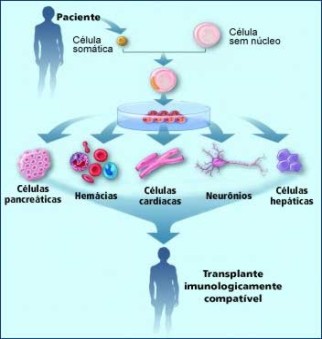

A clonagem terapêutica designa a técnica que tem como objetivo a formação de órgãos ou tecidos para transplante. É um procedimento cujos estágios iniciais são idênticos à clonagem para fins reprodutivos, difere somente no facto do blastocisto não ser introduzido no útero. O blastocisto é utilizado em laboratório para a produção de células totipotentes a fim de produzir tecidos ou órgãos. Esta técnica tem como objetivo produzir uma cópia saudável do tecido ou do órgão de uma pessoa doente para transplante.

Figura 5 – Processo de clonagem terapêutica.